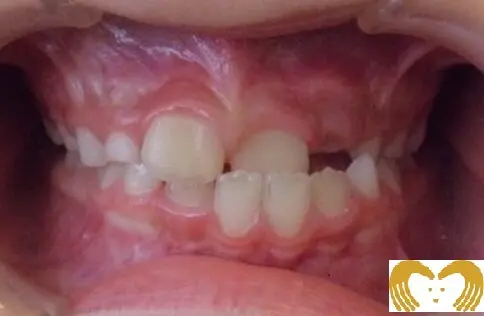

引用元URL:https://www.ortho-sakaiclinic.jp/16703140325782症例01:交叉咬合

《Before》《After》

- 年齢:

- 7~12歳

- 性別:

- 女の子

- 治療内容:

- ネオキャップシステムによる、交叉咬合の治療

- 治療回数・期間:

- 約5年間

- 治療費:

- 495,000円(税込)

- リスク:

- 取り外し可能な装置の為、治療の効果が使用頻度に左右されます。